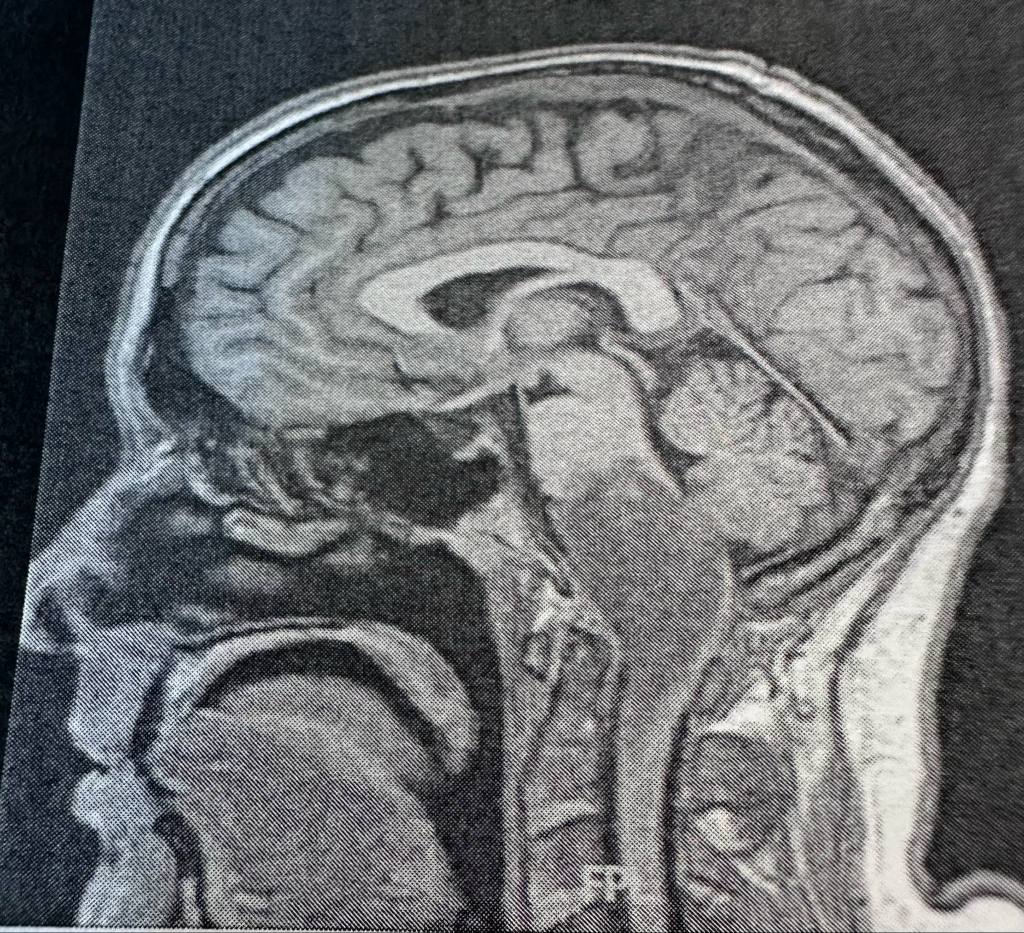

I’m here, doing well. Kinda nervous for the upcoming chemo but it’s my first time with it. I’ll let you know when that all starts. I have a mask fitting next Friday for Radiation therapy. Oh that reminds me, at the Neuro appt this past Friday, they said Proton could be done at a different location. But what they neglected to tell me was it was downtown, ok downtown Tampa, not too bad…NO! it was downtown Orlando. Um no thank you. That’s way too far to go. Especially to be there at 8am on a Friday. I think not. I don’t even want to go back to Riverview which is only 40mins. Orlando would be near double that and more. Y’all nuts.